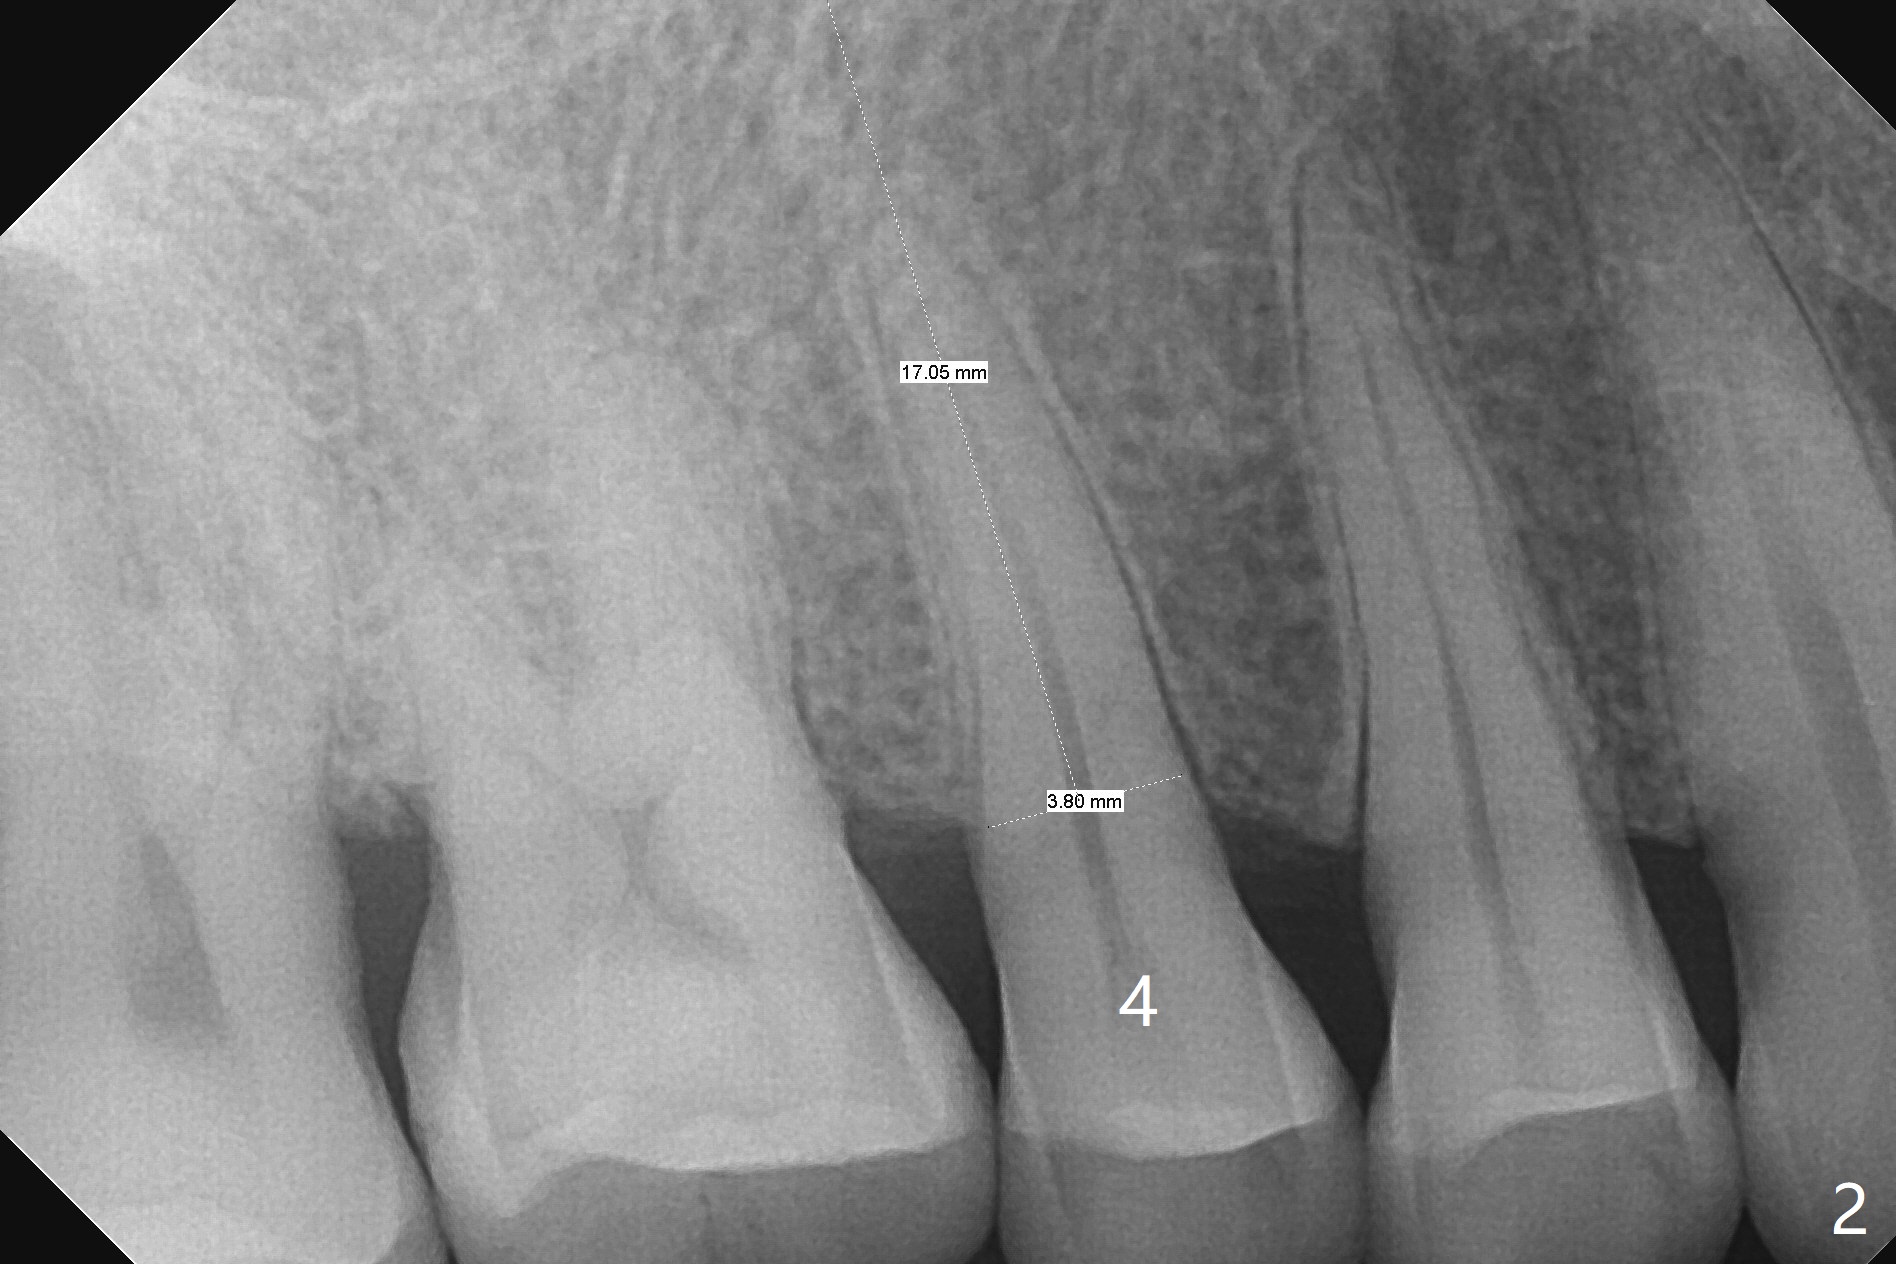

A 61-year-old man cracks the tooth #4 while chewing on a piece of chicken bone (Fig.1,2). Initial osteotomy appears to be able to hold a 16 mm long implant (Fig.3). After sequential osteotomy, a 4x16 mm implant is initially unable to be seated low enough for the buccal crest. Following packing the osteotomy with Vanilla Graft (.5-1 mm) and additional 2-3 mm depth of osteotomy, the implant is placed slightly apical to the buccal crest (Fig.4,5); with placement of Vanilla Graft (*) and a 4.5x4(4) mm abutment, an immediate provisional is fabricated to close the socket. The provisional is removed 3 months postop because of poor local oral hygiene (Fig.6,7). The gingiva is healthy 2-3 weeks later; it is easy to take impression (Fig.8).